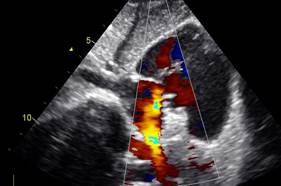

Se verifica con doppler color y espectral el adecuado flujo de la vena cava superior y de la vena pulmonar derecha en la zona próxima a la colocación del oclusor. (Figuras 11,12,13)